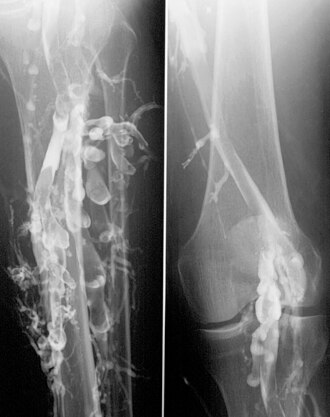

Flebografija kod duboke venske tromboze nogu